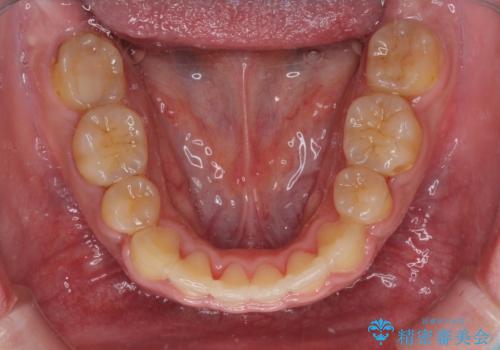

- 口元の突出感と上下前歯のでこぼこを気にして来院された患者様です。

上下前歯部叢生のスペース獲得のため、上下顎左右小臼歯各1歯(計4本)を抜歯して、矯正治療を行うこととしました。

口腔内の清掃性に問題があり、虫歯のリスクが極めて高かったため、短期で治療を終えることを最優先に治療を進めました。